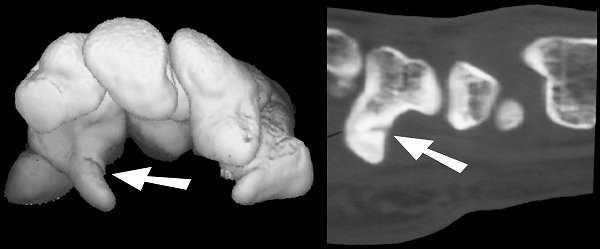

Figure Legend: Hook of hamate fractures

may not be adequately visualized even on multiple specialty views, particularly

when they are nondisplaced. Many if not most hook of hamate fractures

progress to non-union, and pose an ongoing risk for flexor tendon ruptures.

Patients may remain symptomatic and are at risk for tendon complications

from partial unions as well. Such fractures require high-definition CT

scans or trispiral tomography for diagnosis. These CT images demonstrate

a partial union seen on 3D reconstruction (left) and longitudinal reconstructions

(right) despite normal plain films.